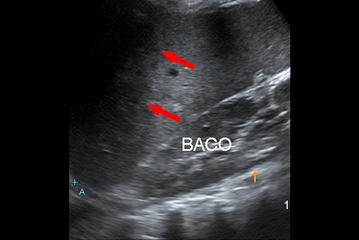

Descrição das figuras: Paciente pediátrico, portador de anemia falciforme com dor em hipocôndrio esquerdo. Na ultrassonografia observa-se lesão em cunha, com formato triangular, hipoecoico e, durante a avaliação com Doppler colorido, não há fluxo nesta região (setas vermelhas e amarela), confirmando a possibilidade de isquemia/infarto.

• Ultrassonografia do abdome: Observaremos lesão em cunha, com formato triangular, hipoecoica e, durante a avaliação com Doppler colorido, não há fluxo nesta região (setas vermelhas e amarela), confirmando a possibilidade de isquemia/infarto (figuras acima) .